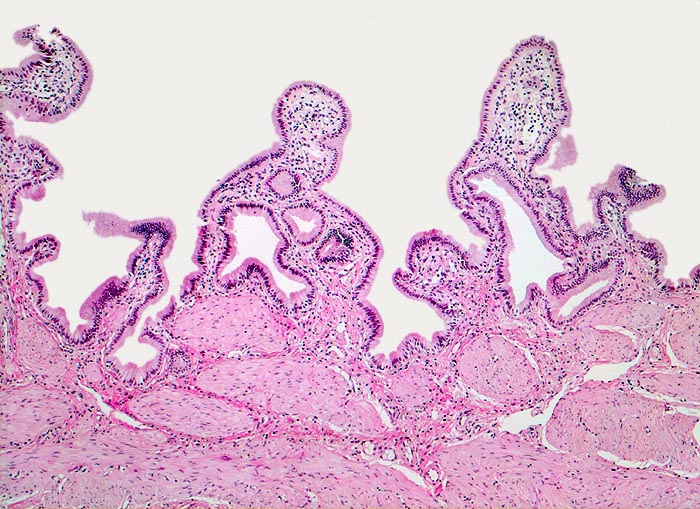

Normale Gallenblase

Die Gallenblasenschleimhaut bildet unregelmässige Falten, die bedeckt sind von einem hochzylindrischen Epithel. Unterhalb der Mukosa eine dicke Schicht glatter Muskulatur. Anders als in anderen Hohlorganen des Gastrointestinaltrakts fehlen eine Lamina muscularis mucosae und eine Submukosa.

Histologie

50